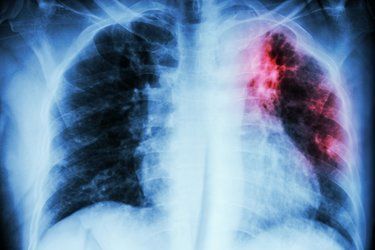

Ankara Ülkemizde de akciğer kanseri oldukça yaygın görülüyor. 2020 yılında 40 binin üzerinde yeni akciğer tanısı konulduğu belirtiliyor. Akciğer kanseri, genellikle erken dönemlerinde fazla belirti vermemesi veya en tipik belirtisi olan öksürük geliştiğinde sigara içen kişilerin ‘sigara öksürtüyor’ düşüncesiyle hekime geç başvurmaları nedeniyle sıklıkla ileri evrede teşhis ediliyor. Tedavinin gecikmesi de hastanın hayatını kaybetmesine yol açıyor. Acıbadem Ataşehir Hastanesi Göğüs Cerrahisi Uzmanı Prof. Dr. Erdal Okur, oysa gerek cerrahi tedavide gerekse diğer tedavi yöntemlerinde yaşanan önemli gelişmeler sayesinde özellikle erken tanı konabilen ve cerrahi olarak tedavi edilebilen akciğer kanserinden tamamen kurtulmanın mümkün olabileceğini belirterek, “Hastalığın erken döneminde tanı konabilmesi için yüksek riskli olarak belirlenmiş, yoğun sigara içen veya geçmişte içmiş olan 50 yaş üzeri kişilere her yıl düşük radyasyon dozlu bilgisayarlı akciğer tomografi çekimi yapılması öneriliyor. Bu sayede henüz hiçbir belirti vermemiş erken evre akciğer kanserinin yakalanması mümkün olabiliyor” diyor. Peki hangi belirtiler akciğer kanserine işaret ediyor, ne zaman hekime başvurmak gerekiyor? Göğüs Cerrahisi Uzmanı Prof. Dr. Erdal Okur, “1-30 Kasım Dünya Akciğer Kanseri Farkındalık Ayı” kapsamında akciğer kanserinin belirtilerini anlattı; önemli uyarılarda bulundu!